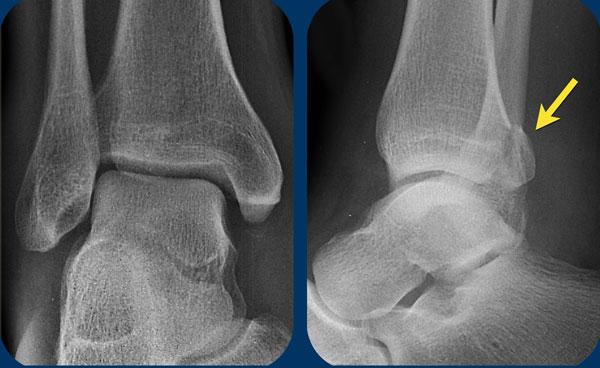

Hãy nghiên cứu các hình ảnh.

Sử dụng thuật toán và tự hỏi liệu đây là Weber A, B hay có thể là Weber C.

Sau đó xác định giai đoạn tổn thương.

Tiếp tục để xem phần thảo luận về ca lâm sàng này.

- Thoạt nhìn, có vẻ như chỉ có đơn thuần gãy mắt cá sau (tertius).

- Khi nhìn vào thuật toán, có thể thấy rằng gãy mắt cá sau có thể gặp trong gãy Weber B ở giai đoạn 3 và trong gãy Weber C ở giai đoạn 4.

Vì bệnh nhân này không có Weber B, đây phải là gãy xương Weber C. Gãy mắt cá sau đơn độc rất hiếm gặp và có lẽ không tồn tại. - Bây giờ chúng ta nhận ra phù nề phần mềm ở phía trong, đây là giai đoạn 1.

- Trên hình phóng to, chúng ta cũng nhận ra một mảnh gãy avulsion nhỏ.

Sau khi phát hiện giai đoạn 1 và 4 của cơ chế chấn thương kiểu Weber C, chúng ta có thể chắc chắn rằng cũng phải tồn tại giai đoạn 3, tức là gãy xương mác ở vị trí cao.